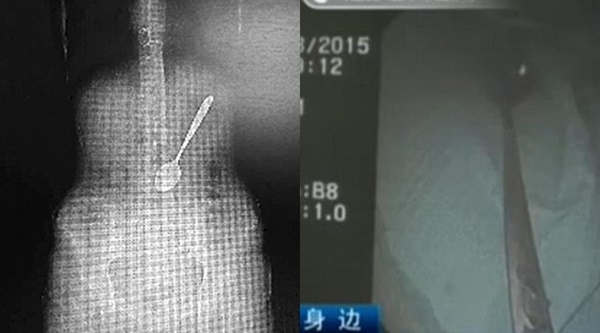

Setelah dilakukan berbagai pemeriksaan, kondisi dari wanita ini pun menjadi lebih serius dari yang telah diperkirakan sebelumnya. Dari hasil pemeriksaan dengan menggunakan sinar X, tampak sendok tersebut memiliki panjang sekitar 15 sentimeter.